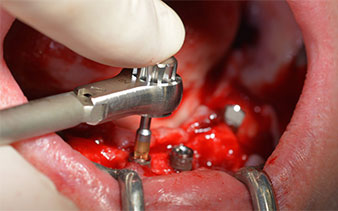

Prima di tutto, è stato individuato il forame mentoniero come limite della struttura anatomica. Successivamente, l'osso corticale della cresta è stato lisciato con un manipolo e una fresa larga a rosetta (Fig. 4).